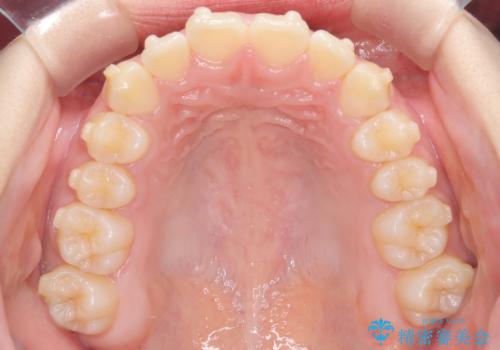

- 患者様は、**下の前歯のがたつき(叢生)**を気にされて来院されました。

できるだけ目立たずに治療を進めたいというご希望があったため、インビザラインによるマウスピース矯正をご提案しました。

診査の結果、インビザラインでの対応が可能と判断し、全体の咬合バランスにも配慮した上で、治療計画を立てました。

下の前歯のがたつきは解消され、滑らかなアーチ状の歯並びとなりました。

目立たずに治療が進んだことに対しても、患者様から高い満足のお声をいただきました。